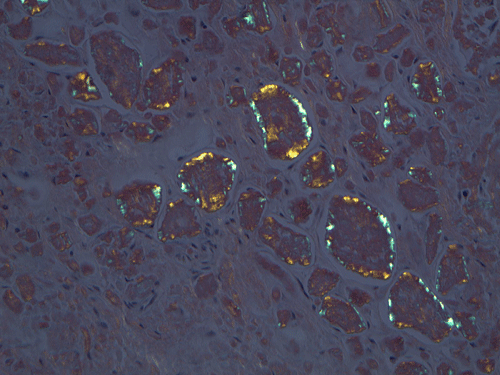

On low magnification, the mucosa appear intact and unremarkable. However, the submosa and muscular layer is replaced by a pale eosinophilic, hypocellular, amorphous material (Panel A). These material separate the smooth muscle bundles (Panel B and C). On Masson's trichrome, these material appears blue (Panel D). They are negative for elastic stain (Panel E). These material are stained orange by Congo Red stain (Panel  F and G) which gives an apple green birefrigence on polarized light (Panel H). Electron microscopy was performed and revealed non-branhing straight fibrils ranging from 6.6 to 8.3 nm in diameter consistent with amyloid.